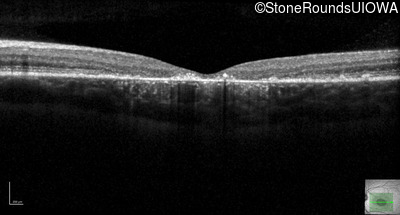

Optical Coherence Tomography - Right - 20/125 sc

Exemplar / OCT Stack